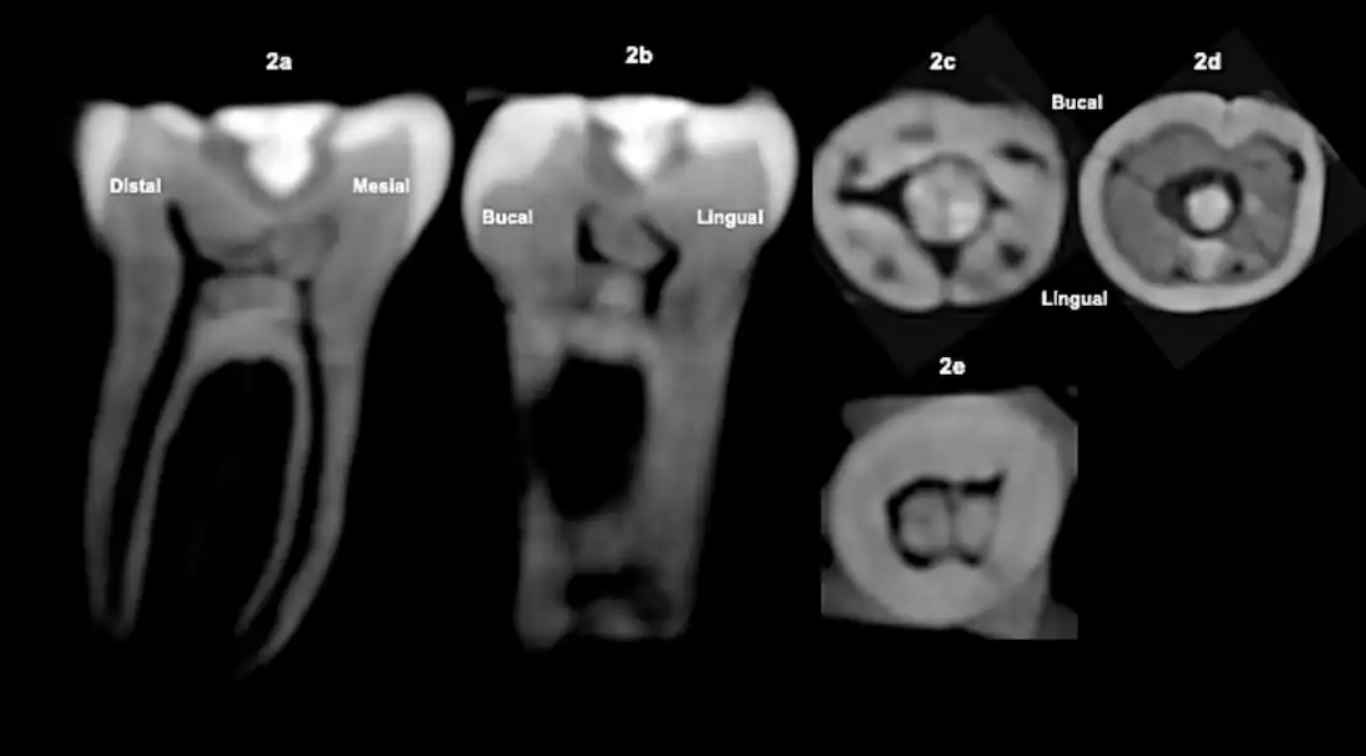

Для аналізу внутрішньої структури зуба без його пошкодження науковці використали конусно-променеву комп'ютерну томографію (КЛКТ). Сканування показало наявність кальцифікації в пульповій камері безпосередньо під місцем втручання. Такі відкладення мінералів є біологічною реакцією живої тканини на травму, спричинену свердлінням. Це остаточно спростовує версію про те, що камінь могли вставити після смерті в ритуальних цілях. Аналіз також дозволив встановити вік пацієнта – це була молода людина 24-30 років.

Досліджений об’єкт – перший нижній моляр лівого боку, що належить до доіспанського періоду. В самому центрі жувальної поверхні вчені виявили ідеально підігнану вставку з зеленого каменю, найімовірніше, жадеїту. Цей матеріал мав надзвичайно високу цінність у культурі мая.

Важливою особливістю є те, що камінь розташований врівень із поверхнею зуба, що дозволяло людині вільно жувати, не відчуваючи дискомфорту. Це свідчить про те, що стародавній майстер точно розрахував глибину та форму отвору.